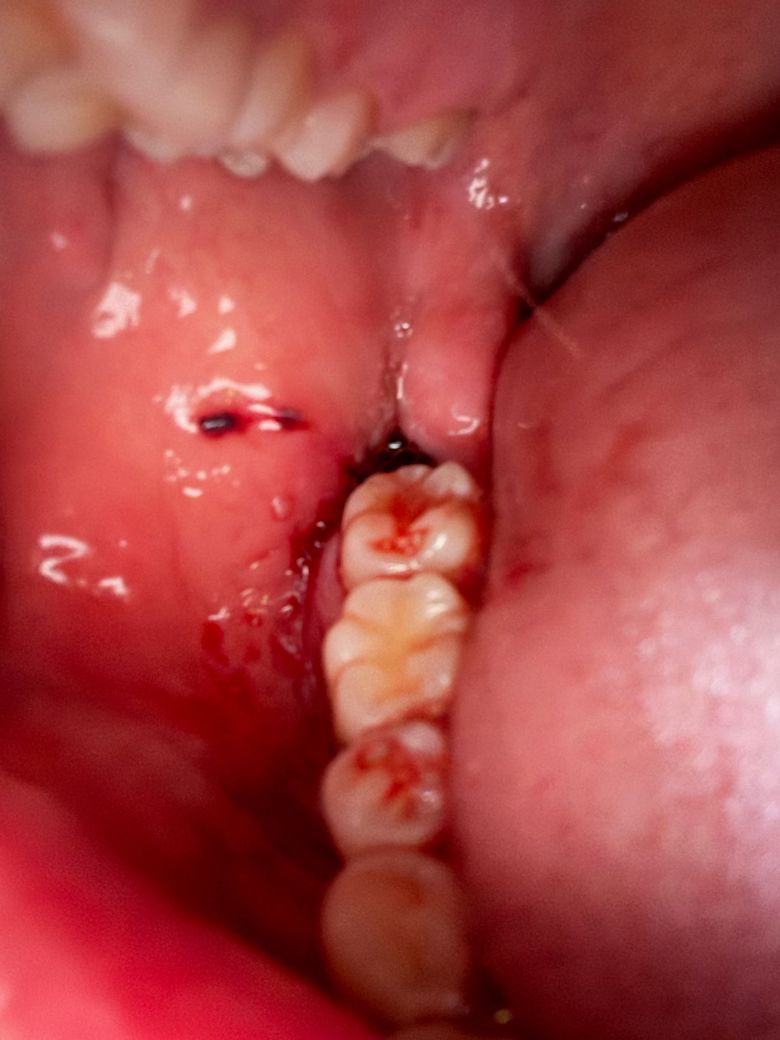

사랑니발치하고 현재 출혈이 멈춘 상태인가요?

오후2시쯤 뽑고 거즈물고 병원가서 5시쯤 거즈새로갈고 꾹물다가 오후8시쯤 땠어요.

침이 많이나와서 자주삼키는데 피는 고일정도로는 흐르진않는거같고 발치한부분잇몸으로 조금 흘러멈춘정도로 나온거같아요. 지혈된건가요???

• 1번 째 사진

사랑니발치하고 현재 출혈이 멈춘 상태인가요? -> 네 출혈이 심하지 않아보입니다 너무 걱정마세요

아직은 지혈이 많이 안된거 같으니 추가로 받으신 거즈를 더 꽉 깨물고 계시는게 좋을것같습니다.

사진으로 봤을 경우에는 아직 출혈이 되고 있는 것으로 보입니다. 사랑니를 발치한 부위가 자극되지 않도록 하시고 거즈를 더 물고 있는 것이 좋을 것으로 생각됩니다

지혈은, 된 것이 맞으며 어느정도. 피가 새어나오는 것은 며칠 정도는 더 지속될 것 입니다.